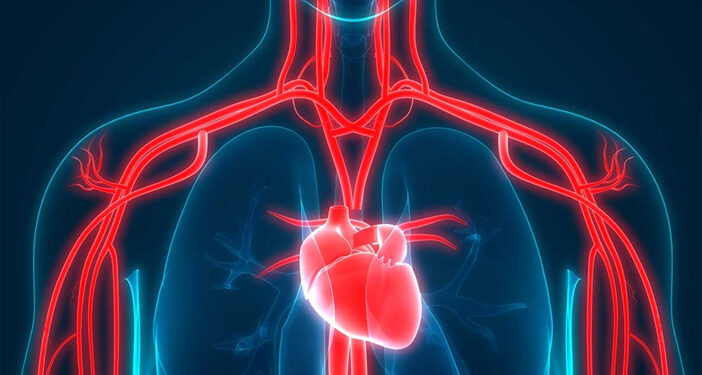

Consider your coronary arteries to be expressways that carry oxygenated blood to your heart muscle. These can narrow or become clogged over time, as a result of plaque development, a condition known as atherosclerosis. When blood flow is impeded, the risk of heart attacks, strokes, and even sudden death rises dramatically.

Traditional coronary artery bypass grafting (CABG) creates new blood flow routes by connecting arteries and veins. While successful, studies and experience show that arterial grafts, particularly those taken from the chest and arm, endure significantly longer than vein grafts from the legs.

Total Arterial Bypass Surgery uses only arterial grafts (rather than a combination of arteries and veins), to reroute blood around blocked heart vessels. The internal mammary arteries (from the chest) and the radial arteries (from the forearm) are frequently utilized.

Why choose all-arterial? Arteries are designed to tolerate high pressure and are more resistant to wear and tear from blood flow. Simply put, they are stronger, more robust, and remain open longer.